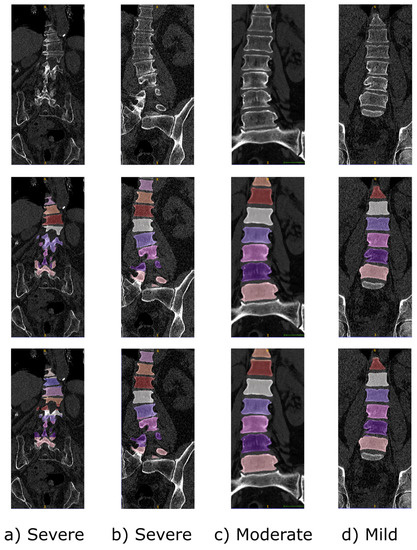

- Slice Extraction. The algorithm extracts a 2D sagittal slice from the binary segmentation, starting from the middle of the image, since it has a higher probability of showing well-clustered vertebrae. Kindly note that, in some cases, e.g., patients affected by severe scoliosis, this consideration may not hold, resulting in lower segmentation performances. Inside the selected slice, the following sub-steps have been carried out:

- Löffler, M.T.; Sekuboyina, A.; Jacob, A.; Grau, A.L.; Scharr, A.; El Husseini, M.; Kallweit, M.; Zimmer, C.; Baum, T.; Kirschke, J.S. A Vertebral Segmentation Dataset with Fracture Grading. Radiol. Artif. Intell. 2020, 2, e190138. [Google Scholar] [CrossRef] [PubMed]